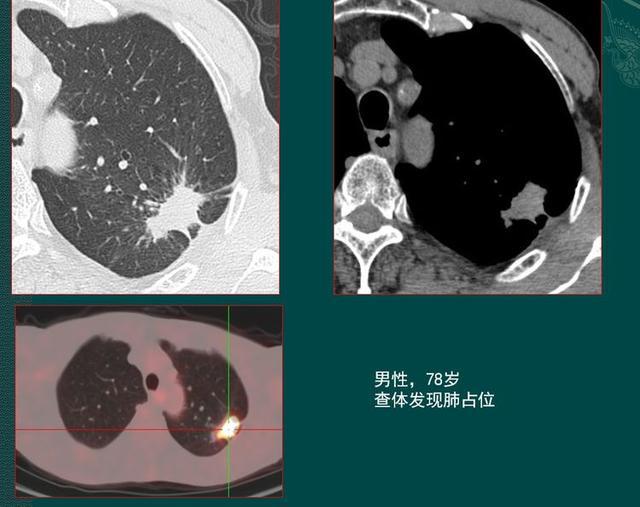

病例来自山东肿瘤医院黄教授

上面这位78岁老爷子,胸部CT发现左上肺团块影,形态不规则,边缘有毛刺和胸膜牵拉,没有钙化和空洞形成,病人经济条件还好,直接花几千块做了PET-CT,显示病灶内高浓聚(左下图黄白色区域),在多家医院诊断为肺癌,准备手术切除。

这个病例提醒我们,PET-CT(派克)对于判断某些病灶的良恶性并不具明显优势,不过它对评估肿瘤的分期很有价值,可以手术前排查有无全身播散。

相信只凭这些资料,任何医生都不敢排除肺癌。这时候该怎么办呢?

病人的儿子带着片子去找了黄教授会诊,黄教授建议先做个增强CT,看看病灶内有无血供。

1.陈旧性结核灶里面的血管会被结核杆菌破坏掉,增强扫描是不强化的(活动期可见强化,多为包膜样强化);

2.如果是肺癌,里面会有杂乱血管滋养癌细胞,增强CT多呈现轻中度不均匀强化,通过测量CT至可以明确。

老爷子后来预约了增强CT,显示病灶没有强化,动脉期和静脉期病灶密度没有增加,说明高密度的造影剂随血液循环过来后,进不去病灶内部,里面没有血管,提示为陈旧性肺结核。

为求万全之策,又做了经皮肺穿刺,发现肺结核特有的干酪样坏死物,没有癌细胞,老人避免了手术创伤。嗯,也省了一笔钱。

这个病例告诉我们,当从形态特点上无法鉴别肺结核与肺癌时,增强CT有时会提供有价值线索。